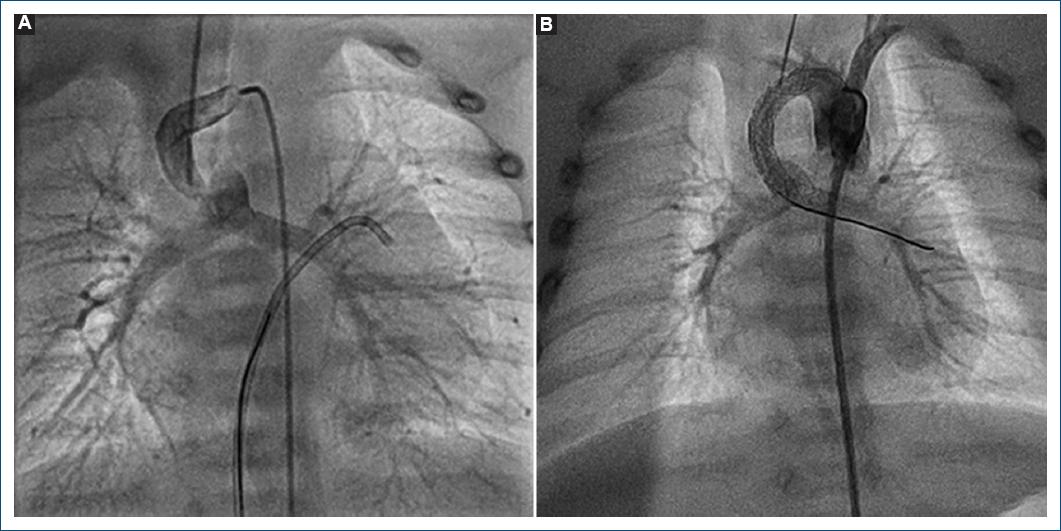

Los procedimientos fueron llevados a cabo en el servicio de hemodinamia del Hospital Garrahan, formado por cuatro hemodinamistas con años de experiencia en el tratamiento de cardiopatías congénitas de pacientes recién nacidos. La distribución de los casos fue similar entre estos. Todos los pacientes fueron planteados para el procedimiento luego de realizar el diagnóstico inicial con ecocardiograma. En algunos casos fue necesario realizar angio-TC con contraste para definir adecuadamente la morfología del conducto, y en unos pocos casos el cateterismo diagnóstico inicial se utilizó para plantear la posibilidad de implantar un stent ductal. En la actualidad se encuentra protocolizada la realización de angio-TC en aquellos pacientes en quienes se plantee la colocación de un stent en el conducto arterioso para definir con mayor certeza la morfología ductal. En los casos que correspondía se suspendió el goteo de prostaglandinas 12 horas antes para favorecer la constricción pulmonar. Para el procedimiento, todos los pacientes requirieron anestesia general con asistencia respiratoria mecánica. En la mayoría de los casos el acceso vascular utilizado fue tanto arterial como venoso, y los introductores oscilaron entre 3 y 5 Fr. En cuatro pacientes el acceso arterial fue carotídeo por el origen del conducto arterioso desde el tronco braquiocefálico. Se utilizaron stents coronarios no farmacológicos con diámetros entre 3.5 y 4.5 mm y de longitud variable. En siete casos fue necesario el implante de dos stents para mantener la permeabilidad del conducto arterioso (Figs. 1 y 2). Al finalizar el procedimiento se efectuó angiografía de control para certificar el buen funcionamiento del stent y su permeabilidad, y luego, con una saturación acorde al modelo hemodinámico, se finalizó el procedimiento y los pacientes pasaron a la unidad de cuidados intensivos (Fig. 3). Posterior al procedimiento se encuentra protocolizado mantener anticoagulación con heparina por 48 horas y luego iniciar antiagregación con ácido acetilsalicílico.

Figura 1 A: angiografía que evidencia el origen del conducto arterioso en el tronco braquiocefálico derecho en un paciente con ventrículo único con atresia pulmonar con arco aórtico izquierdo. B: angiografía tras la angioplastia con colocación de dos stents.

Figura 2 A: angiografía que evidencia origen del conducto arterioso en el tronco braquiocefálico izquierdo en un paciente con tetralogía de Fallot y arco aórtico derecho. Se evidencia algo de tortuosidad y constricción en el tercio proximal a la arteria pulmonar. B: angiografía tras la angioplastia con colocación de dos stents.